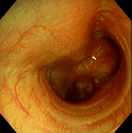

胃腺癌

炎症性ポリープ

炎症性ポリープ⑵

慢性腸症(犬)

慢性腸症(猫)